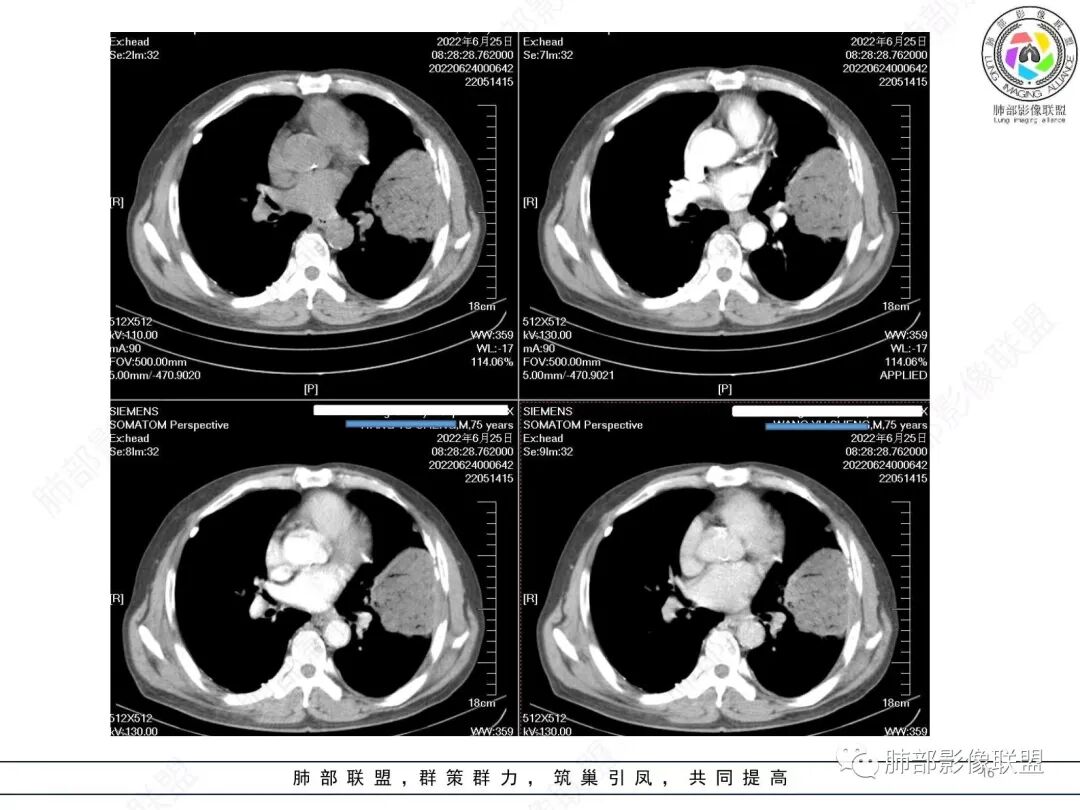

南边:

我再建一下血管。支气管进入,但是近端推移,堵塞

大肿块,边缘光滑,深分叶

近端支气管堵塞、推移为主

部分类似于脐凹征

内部支气管扩张

肺动脉推移为主,边缘部分进入

淋巴瘤符合吗?

尘缘:

淋巴瘤肯定不符合了。

仅仅只有血管漂浮和支扩支持淋巴瘤。其他细节都是否定淋巴瘤的。

大肿块、表面光滑但深分叶,肺门侧支气管堵塞

我一开始诊断恶性,定在淋巴瘤,还觉得信心满满

回头看,内部支气管近端其实不连续,伴随肺动脉不存在

这两点就不符合

还有如果从支气管的特点考虑黏膜相关性淋巴瘤,其整体应该是边缘不清楚为主,肺炎样为主。